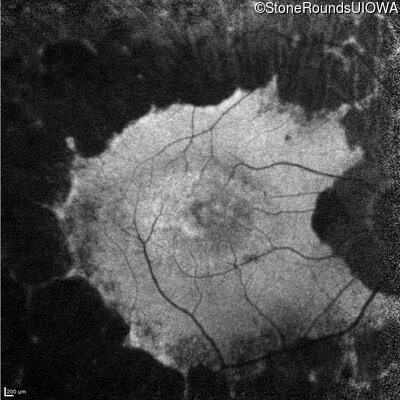

Infrared Fundus Photograph - Right - 20/50 -1

Exemplar